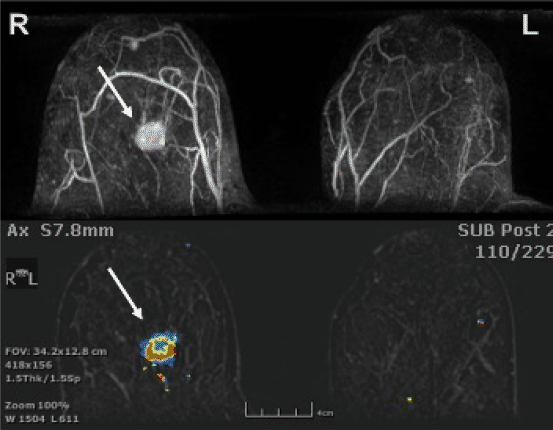

Borstvoeding Geeft u borstvoeding dan moet u de melk tot 24 uur na het onderzoek niet gebruiken maar afkolven en weggooien. Een MRI-onderzoek van de borsten kan niet plaatsvinden wanneer u borstvoeding geeft. Contrast media and breastfeeding is an area of imaging safety that has been investigated for both iodinated and gadolinium-based contrast agents. Contrast is a type of dye that is injected intravenously either right before or during the procedure. Gezien pathologie vaak gepaard gaat met vocht heeft een combinatie van contrast. Volgens de bijsluiters van de contrastmiddelen raadt men echter nog steeds aan 1 dag te stoppen met de borstvoeding.